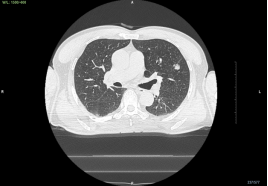

王大伯术前CT

尽管结节比一颗花生大不了多少,但凭借团队医生高超的技术,以及呼吸内镜中心导航系统及DSA的加持,穿刺针穿过管壁,顺利找到了病灶,为了多维度保证位置的准确,介入团队此次利用高大上的锥形束CT进行术中实时定位,确保万无一失。

CBCT确认活检钳位置准确无误,术者开始活检,取材满意。术中快速现场细胞学评估提示腺癌。

局部CT术前后对比,原病灶完全被消融范围所覆盖